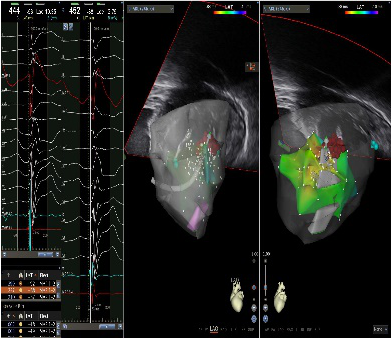

5月25日,心血管内科电生理团队独立应用心腔内超声(CartoSound)导管结合三维标测系统完成我首例乳头肌室性早搏射频消融术及房颤射频消融术。

第1例患者,男性,61岁。发现室性早搏5年,动态心电图提示24小时室早总数35000+次,口服药物效果不佳,需要行射频消融术治疗。但该患者心电图表现提示为乳头肌起源室性早搏,由于乳头肌本身结构复杂,毗邻组织较多,常规的三维电解剖标测系统不能充分显示乳头肌结构,而且射频导管也很难准确到位和稳定贴靠,所以该区域的室早射频消融难度较高,普通的三维标测射频消融术费时费力,成功率低,复发率高。使用心腔内超声技术(ICE)可以帮助介入医生更加直观地看到乳头肌位置,还可以更加精确地定位消融导管的位置,实时显示导管贴靠的情况,显著提高了手术的成功率,同时有效减少X线的用量,减轻辐射对病人和医生的伤害。

第2例患者,男性,51岁。诊断阵发性房颤5年,该例手术是省内第一次独立应用ICE完成的零射线房间隔穿刺及房颤射频消融手术。手术用时1.5小时,术中一切顺利。

目前,心腔内三维超声技术在美国、欧洲和日本等国家的大型医学中心用于各类复杂心律失常的介入治疗。我院心血管中心首次独立将CartoSound心腔内三维超声技术用于难治性室性早搏和心房颤动的治疗。本例手术的成功,标志着心血管内科在绿色电生理射频消融治疗心律失常疾病方面有了进一步的提高,将为更多心律失常患者带来福音。